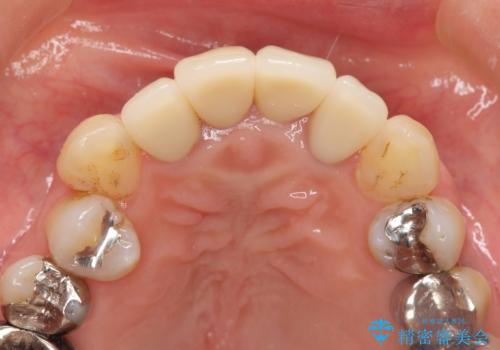

クラウンを除去し審美的なジルコニアクラウンによる補綴の再作製計画を立案します。

- 52万円(仮歯×4・ファイバーコア×4・ジルコニアクラウン×4)費用は治療当時の料金となります